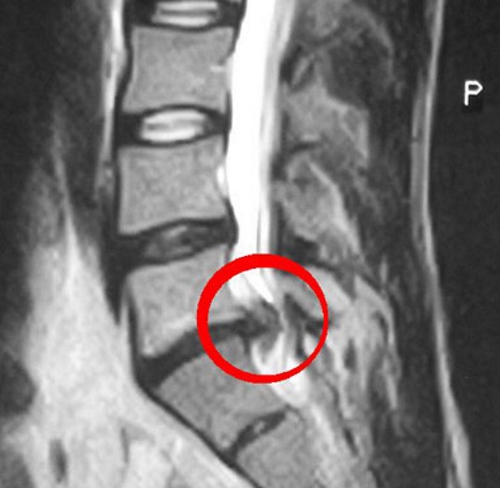

Существует множество методов консервативного лечения, которые помогают справляться с симптомами заболевания и предотвращают его рецидивы. В большинстве случаев, около 95% пациентов могут быть вылечены без хирургического вмешательства. При выборе между консервативным и хирургическим подходами врачи учитывают ключевой фактор — размер грыжи. Для этого применяются различные виды диагностики:

- МРТ;

Размер грыжи, который играет решающую роль в принятии решения о необходимости операции, зависит от отдела позвоночника, в котором она расположена. Протрузии в поясничном и грудном отделах до 12 мм могут успешно лечиться консервативно, что дает пациенту шанс избежать операции. В то же время для шейной грыжи размер в 7 мм уже считается критическим, и вероятность хирургического вмешательства в таких случаях значительно возрастает.

Показания к операции не ограничиваются только размером грыжи; они также зависят от ущемления спинного мозга или нервных корешков. Хирургическое вмешательство может быть рекомендовано, если длительное консервативное лечение не приносит облегчения, и болевой синдром сохраняется.

Когда протрузия достигает 12 мм и более, обычно требуется операция. Это особенно актуально, если происходит сжатие нервных корешков, известных как конский хвост. При их сдавливании у пациента может возникнуть паралич нижней части тела. В таких ситуациях операция по удалению грыжи позвоночника становится единственным способом сохранить или восстановить двигательную активность пациента.